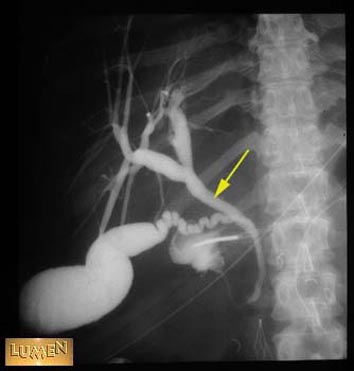

Common hepatic duct.